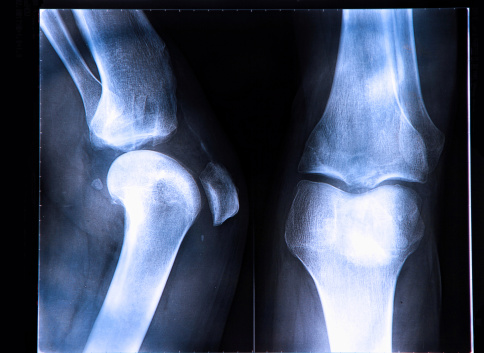

The over-consumption of fluoride can have a multitude of side-effects. In minor cases, you may experience severe stomach pains, nausea, or other gastrointestinal symptoms. In more severe cases, too much fluoride can lead to a bone disease known as skeletal fluorosis. Symptoms include joint pain, swelling, increased risk and frequency of fractures, and decreased joint mobility. People who suffer from skeletal fluorosis are also more prone to hip fractures.

In one extreme instance, a woman had been drinking tea literally by the gallon (up to two gallons a day) for decades, before developing a hunchback and complaining of growing pains and stiffness in her joints and aching bones. X-ray analysis revealed that she suffered from overly dense bones and inflexible joint cartilage, due to long-term excessive consumption of fluoride. After a more extensive review of her history, doctors were shocked to discover that the source of her problems came from her very own home-brewed black tea.